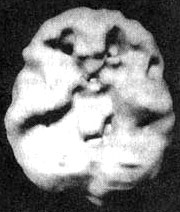

Раньше СДВ рассматривали как некоторое нарушение, имевшееся у гиперактивных мальчишек и компенсировавшееся по мере того, как они взрослели. Сегодня мы знаем, что многие, страдающие СДВ, с возрастом не избавляются от этих симптомов и что это нарушение часто встречается не только у представителей мужского пола, но и у девочек и женщин. По некоторым подсчетам, в США численность страдающих СДВ доходит до 17 млн человек. Кент Когда мы познакомились, ему было 24 года. Он обратился за помощью, так как к тому времени три года просидел на первом курсе колледжа. Он не мог сдать экзамены за первый курс. Он хотел поступать на медицинский факультет университета. Все говорили ему, что он «рехнулся»! Как он мог рассчитывать поступить на медицинский факультет, если был не в состоянии сдать экзамен за первый курс колледжа? Однако потом его мать прочла книгу под названием «Окна в сознание с СДВ» и подумала, не с этой ли проблемой столкнулся ее сын. Ознакомившись с историей болезни Кента, я понял, что мы имеем дело с врожденным и недиагностированным случаем СДВ. Еще в детском саду он не мог долго сидеть на месте; он был беспокойным, отвлекающимся, неорганизованным и потому за ним закрепилась репутация неудачника. Отец Кента предложил провести ему сканирование SPECT. Он хотел убедиться в том, что Кент не пытается найти очередной отговорки, которая объясняла бы отсутствие результатов. В состоянии покоя мозг Кента работал нормально. Однако как только Кент постарался сосредоточиться, префронтальная кора «отключилась». Получив результаты клинического исследования и SPECT, я назначил Кенту Adderall, лекарственный стимулятор для лечения симптомов СДВ. Результаты оказались блестящими. В течение следующего семестра он сдал все долги. Через полтора года получил диплом Associate of Arts (ученая степень, которая присваивается по завершении двухлетней программы обучения), а еще через три года получил степень бакалавра по биологии. Он поступил на медицинский факультет! Через несколько месяцев приема Adderall я сделал Кенту повторное сканирование SPECT. Как было видно на снимке, реакция на лечение была не просто положительной: после приема препарата активность его префронтальной коры заметно усилилась. Мозг Кента. СДВ. До и во время приема Adderall Трехмерное изображение — нижняя поверхность. ![]() В состоянии покоя — обратите внимание на хорошую активность всего мозга. ![]() Во время концентрации: обратите внимание на выраженное снижение активности в префронтальной коре (см. стрелки). ![]() При концентрации во время приема Adderall — обратите внимание на улучшившуюся активность в мозге в целом. Отношение к Кенту со стороны его отца потрясающе изменилось. Он сказал мне: «Я всегда думал, что он просто ленится. Так грустно думать, что все эти годы он был нездоров, а я просто ругал его за лень. Как же мне хотелось бы вернуть это время назад!» У меня был пациент, владевший 10 компаниями, — ему это было необходимо, чтобы оставаться «в тонусе». Когда мозг работает на «сниженных оборотах», человек чувствует себя некомфортно. Подсознательно такие люди стремятся «завести» свой мозг кофе или сигаретами (и то, и другое — мягкие стимуляторы), ссорами, гневом, быстрым темпом жизни или физической активностью с мощным стимулирующим эффектом, как, например, банджи-джампинг (любителям этого вида развлечений стоит пройти сканирование мозга по поводу СДВ!). СДВ в семье По мнению специалистов, на развитие многих психических нарушений большое влияние оказывает наследственность. Не является исключением и СДВ. Вот история болезни, прослеживающаяся в одной семье. Пол (20 лет) пришел ко мне на прием, так как не мог окончить учебу на последнем курсе колледжа. В классе ему было трудно писать контрольные работы, он не мог сконцентрироваться, а мотивация находилась на довольно низкой отметке. Он стал подумывать о том, чтобы бросить школу и идти работать вместе с отцом. При этом ему совсем не нравилась перспектива бросать учебу за несколько недель до выпуска. Пока я заполнял его историю болезни, Пол успел рассказать мне о том, что раньше у него случались приступы депрессии, которые ему лечили лекарством Prozac без особого успеха. Сканирование SPECT выявило повышенную активность лимбической области (связанную с депрессией) и пониженную активность ПК во время выполнения задания на концентрацию. Я назначил лечение антидепрессантами в сочетании с лекарственными стимуляторами. Результат оказался прекрасным. Он окончил колледж и получил работу, о которой мечтал. Увидев, как помогло лечение ее сыну, мать Пола Пэм пришла ко мне на прием сама. В детстве ей трудно давалось учение. Несмотря на то что она была очень артистичной, ей не особо хотелось учиться, и учителя поставили на ней крест. Уже став взрослой, Пэм вернулась к учебе и получила диплом учительницы начальных классов. Чтобы преподавать в средней школе, ей надо было сдать национальный экзамен для учителей. Все четыре попытки оказались неудачными. Пэм была готова отказаться от этой затеи и пойти учиться по другой специальности, но тут она увидела, как помогло лечение Полу. И тогда она подумала, что, может быть, и ей можно помочь. Ее результаты SPECT были сильно похожи на результаты Пола. Ей было назначено похожее лечение, и через четыре месяца она сдала свой экзамен. После того как в семье появилось два успешно пролеченных случая, Пэм привела ко мне девушку-тинейджера Карен. Как и ее брат, Карен была умным ребенком. Тем не менее ей плохо давалась учеба. К тому времени, как мы встретились, она жила в Лос-Анджелесе и занималась на факультете журналистики. Она жаловалась, что учебный материал для нее слишком труден. Она часто страдала от плохого настроения, беспокойства, легко отвлекалась, была импульсивна и вспыльчива. Несколько лет назад она лечилась от алкоголизма и привыкания к амфетамину. Она рассказала, что алкоголь снимал у нее беспокойство, а амфетамин помогал сосредоточиваться. Результаты SPECT-сканирования у Карен оказались похожи на результаты ее матери и брата. Как только она начала принимать лекарства, в ее состоянии произошли перемены, которым она была очень рада. В классе она могла спокойно сосредоточиться, а задания стала выполнять в два раза быстрее. Уверенность в собственных силах укрепилась настолько, что Карен стала искать работу ведущей в телепрограмме. Раньше ей это даже не пришло бы в голову. Из всех членов семьи с самым сильным нежеланием пришел ко мне их отец — Тим. Он упирался, несмотря на то что и Пол, и Пэм, и Карен говорили ему, что он должен пойти. Он говорил: «Со мной все нормально. Посмотрите, какого успеха я сумел добиться!» Однако в его семье знали и другое. Несмотря на то что Тиму на самом деле принадлежал продуктовый магазин, сам он был замкнутым и отстраненным. Он быстро уставал, легко отвлекался и был довольно разбросанным в работе. Успеха в бизнесе он добился во многом благодаря сильной команде сотрудников, которые и занимались реализацией его идей. Ему было трудно учиться новым играм, например карточным, поэтому он стремился избегать каких-то встреч и общественных мероприятий. Тиму нравились острые ощущения. Например, несмотря на то что ему было уже 45 лет, он любил кататься на мотоцикле. В школе, в последних классах он учился плохо. Несмотря на высокий IQ, с трудом окончил колледж. Он менял одну работу за другой, пока не скопил достаточно денег на то, чтобы купить продуктовый магазин. В конце концов Пэм удалось уговорить Тима пойти ко мне на прием. Сама она уже собиралась с ним разводиться, так как была убеждена, что он ее не любит. Позже он рассказывал мне, что тогда чувствовал себя совершенно опустошенным и эмоционально, и физически, чтобы проводить с ней значительную часть времени. |